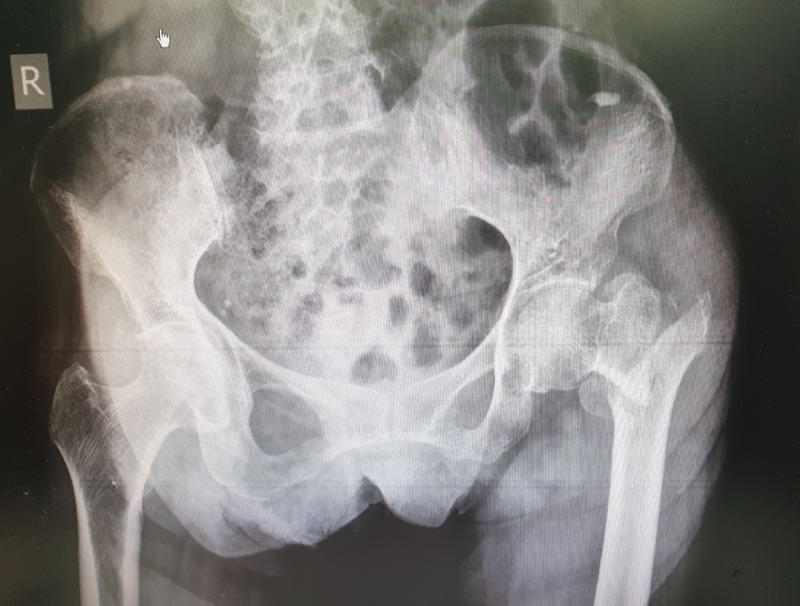

🩻 2. เอกซเรย์ (X-ray)

• การถ่ายเอกซเรย์ เป็นวิธีที่แม่นยำที่สุดในการดูว่ามีกระดูกหักหรือไม่

• ในบางราย กระดูกอาจแตกร้าวเล็ก ๆ จนเอกซเรย์ปกติไม่เห็น